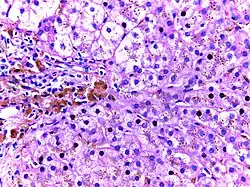

![]() |

Macrophages | Lung showing congestion with plenty of alveolar macrophages containing phagocytosed brownish granular hemosiderin pigment. | Category: Macrophages | Macrophage |